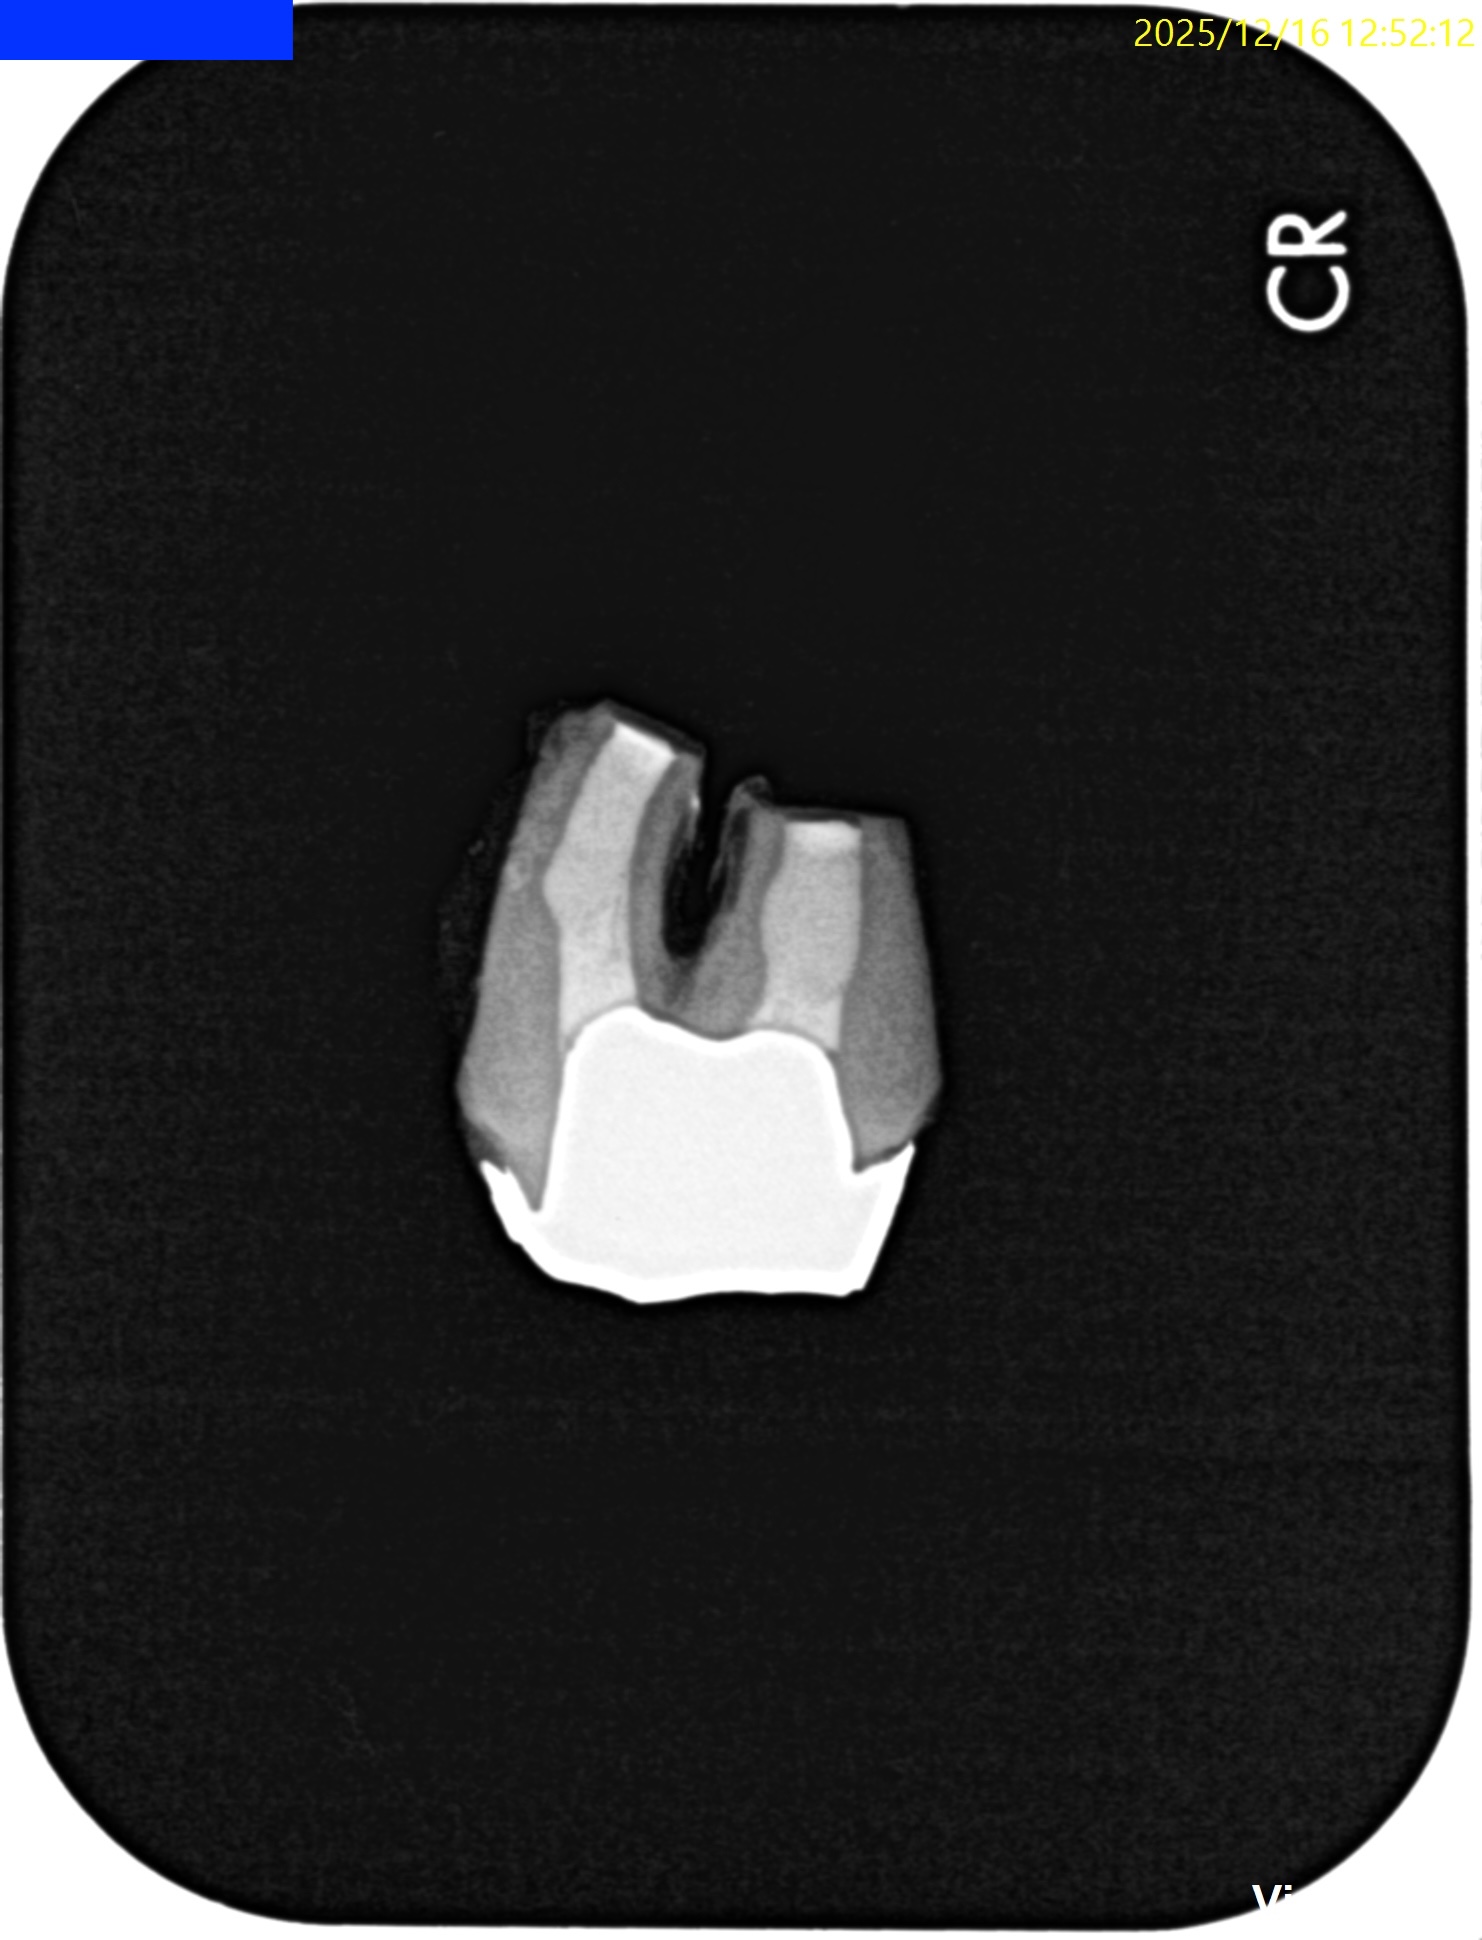

Pre-op Endo test(2025.12.16)

Pulp Dx: Previously treated

Periapical Dx: Symptomatic apical periodontitis

Recommended Tx: Intentional Replantation⇨Core build up